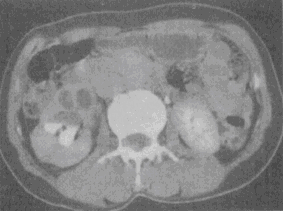

患者,男,33岁,尿频,尿急伴发热月余。尿常规检查:镜下血尿,脓尿。CT检查见图。该患者最有可能患何种疾病

患者,男,33岁,尿频,尿急伴发热月余。尿常规检查:镜下血尿,脓尿。CT检查见图。该患者最有可能患何种疾病<img border="0" style="width:

[单选题]患者,男,33岁,尿频,尿急伴发热月余。尿常规检查:镜下血尿,脓尿。CT检查见图。该患者最有可能患何种疾病A.肾癌B.肾盂癌C.肾结核D.肾囊肿E.错

患者,男,33岁,尿频,尿急伴发热月余。尿常规检查:镜下血尿,脓尿。CT检查见图。该患者最有可能患何种疾病<img border="0" style="width:

[单选题]患者,男,33岁,尿频,尿急伴发热月余。尿常规检查:镜下血尿,脓尿。CT检查见图。该患者最有可能患何种疾病A.肾癌B.肾盂癌C.肾结核D.肾囊肿E.错

患者,男,33岁,尿频,尿急伴发热月余。尿常规检查:镜下血尿,脓尿。CT检查见图。该患者最有可能患何种疾病( )。<br /><img border="0" s

[单选题]患者,男,33岁,尿频,尿急伴发热月余。尿常规检查:镜下血尿,脓尿。CT检查见图。该患者最有可能患何种疾病( )。图1图2图3A.肾癌B.肾盂癌C.

患者,男,33岁,尿频,尿急伴发热月余。尿常规检查:镜下血尿,脓尿。CT检查见图

[单选题]患者,男,33岁,尿频,尿急伴发热月余。尿常规检查:镜下血尿,脓尿。CT检查见图。该患者最有可能患何种疾病()A . 肾癌B . 肾盂癌C . 肾结核D . 肾囊肿E . 错构瘤